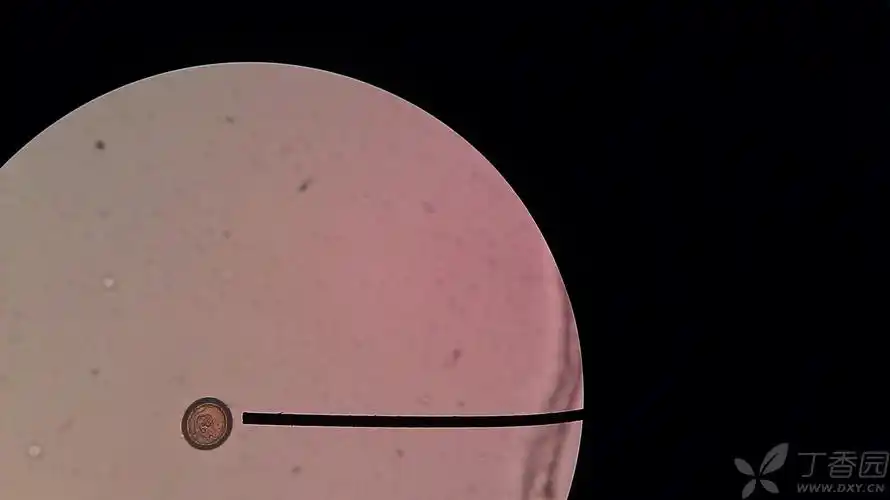

丁香园论坛 - 专业医生社区,医学,药学,生命科学,科研学术交流